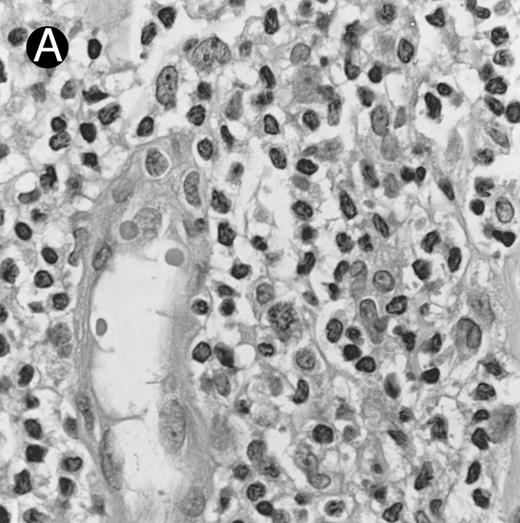

Lymph node biopsy of aggressive NK cell leukemia/lymphoma (case no. 37). There is a fairly monotonous, diffuse infiltrate of medium-sized cells with round nuclei. The neoplastic cells in this case resemble plasmacytoid monocytes.